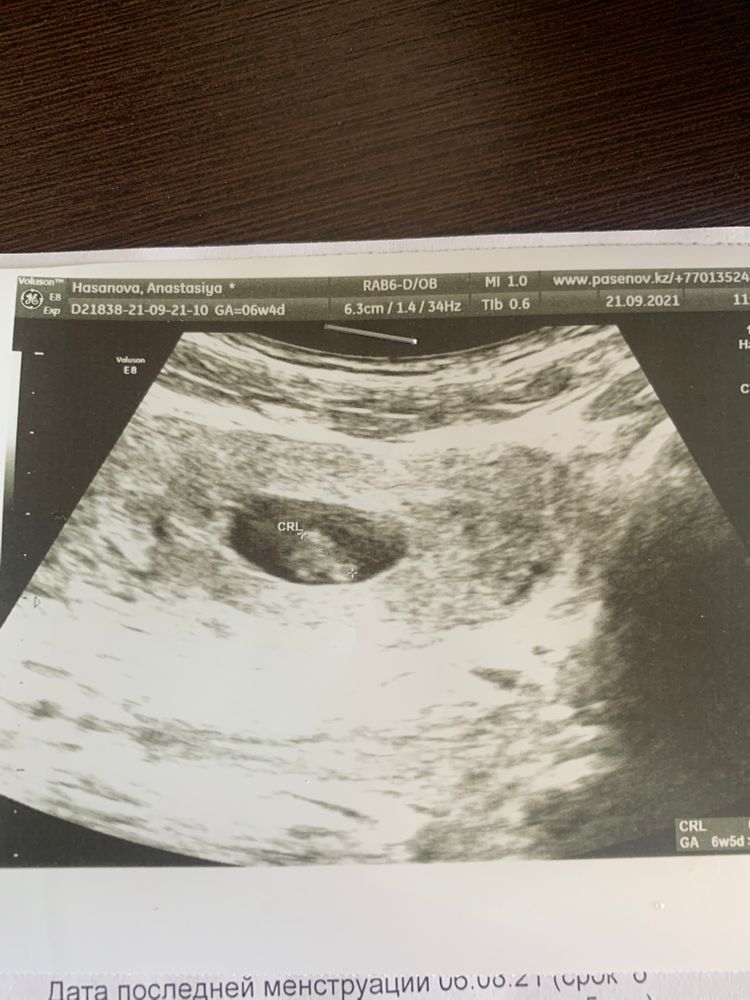

Анастасия Кузнецова, дальнейшие действия такие: когда был 4дз, это уже было 4 недели 2 дня. Я ждала 7ми недель, чтобы уж точно увидеть сердцебиение и эмбрион. До этого времени следила за собой, смотрела данные из приложения для отслеживания Б. Потом на конце 6ой недели записалась к узисту, в день записи было бы 6недель5 дней. Сходила на узи и все) теперь учет и скрининг впереди) советуют сдавать хгч чтобы смотреть динамику, но я купила 7 одинаковых тестов и делала их каждый день до дня узи, просто так, чтобы скоротать время) , на хгч соответственно не ходила, так как тесты ярчали, фото приложу, (после них начала делать те 7 штук; чувств 25, самые дешевые в аптеке). и на этом все) совет: раньше времеНи не ходить на узи, ничего не увидят, а вам лишнее растройство, идите на 7-8 неделе чтоб прям наверняка) я пошла в 6,5 и было ВСЕ- сб, эмбрион, маточная. Фото тоже приложу♥️ Изображение Изображение Изображение